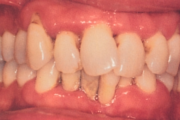

Krooniline parodontiit

Parodontiit